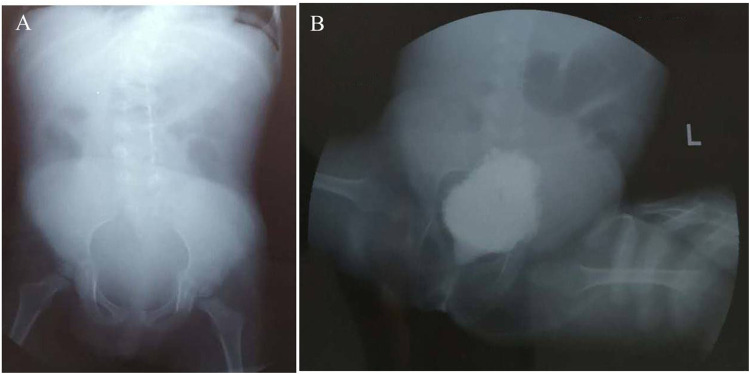

Objective: To describe the clinical manifestations and genetic mutation in a 7-year-old girl presenting with severe scoliosis, hydronephrosis, and other skeletal abnormalities.

Results: Exome sequencing revealed a de novo EBP mutation (c.452A>G, p.Gln151Arg) in the patient.

Conclusion: The patient was diagnosed with X-linked chondrodysplasia punctata type 2 (CDPX2). This novel missense mutation expands the mutation spectrum of CDPX2 and underscores the clinical utility of exome sequencing in diagnosing this condition.